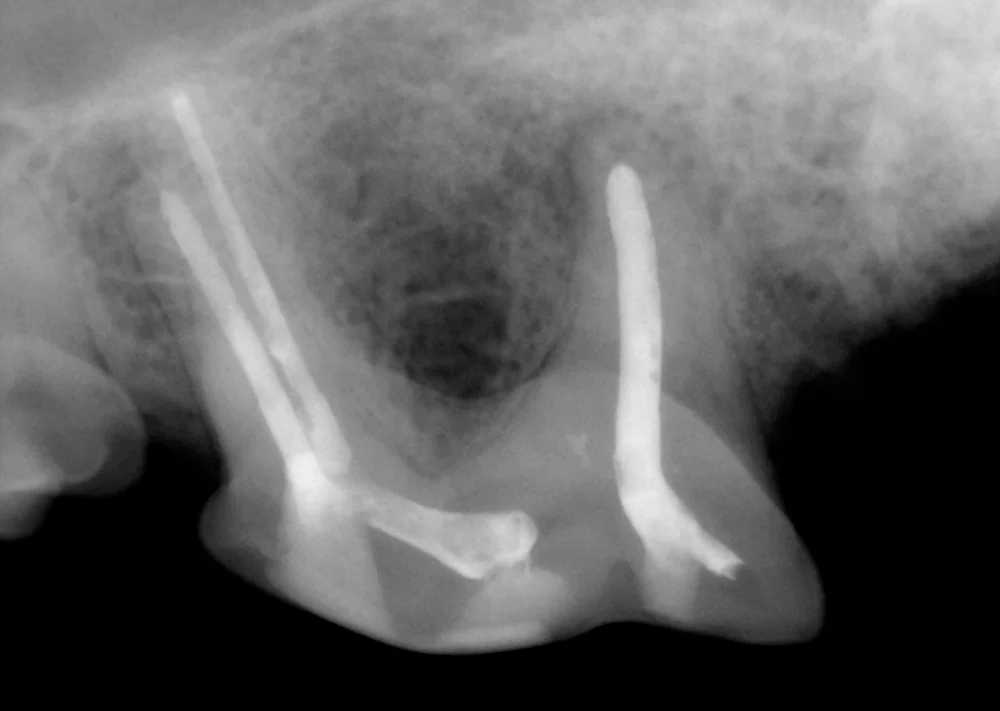

Dental x-rays also help confirm that root canal therapy can be done on a tooth. Sequential x-rays also are taken at each step of the root canal process to help ensure success. To the left is a dental x-ray of a tooth in the middle of the root canal treatment process.